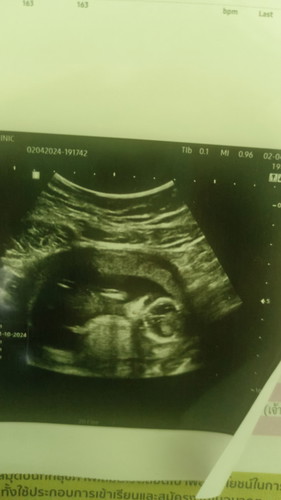

ช่วยดูทีคะว่าเป็นผู้หญิงหรือผู้ชาย

ช่วยดูทีคะน้องเป็นผู้หญิงหรือผู้ชายคะแม่ๆ

อายุครรภ์เท่าไหร่ค่ะ ภาพนี้ไม่สามารถดูเพศได้นะค่ะ